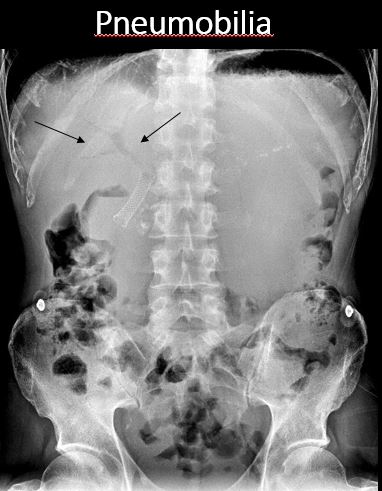

There is pneumobilia. [Yes/No]